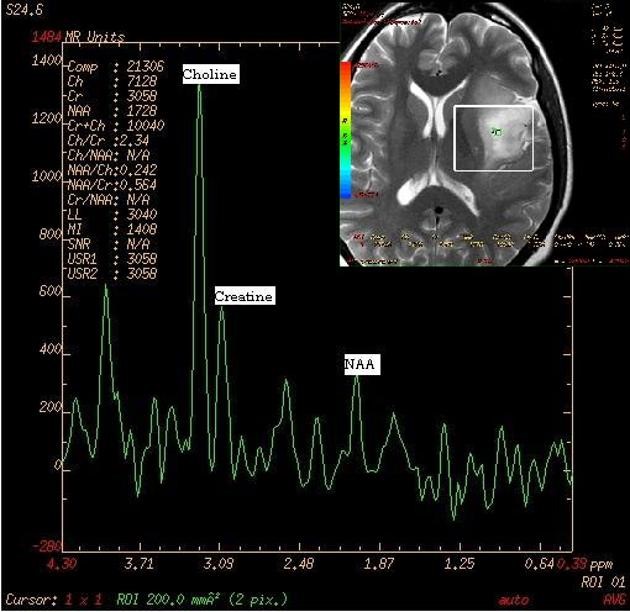

Tôi được bác sĩ khuyên nên thực hiện chụp cộng hưởng từ phổ não (MRI Spectroscopy) để đánh giá thêm về tình trạng tổn thương thần kinh nghi ngờ u não.

Đây là kỹ thuật chuyên sâu giúp đánh giá thành phần chuyển hóa trong tổ chức não, hỗ trợ phân biệt các tổn thương lành tính - ác tính và theo dõi tiến triển sau điều trị.